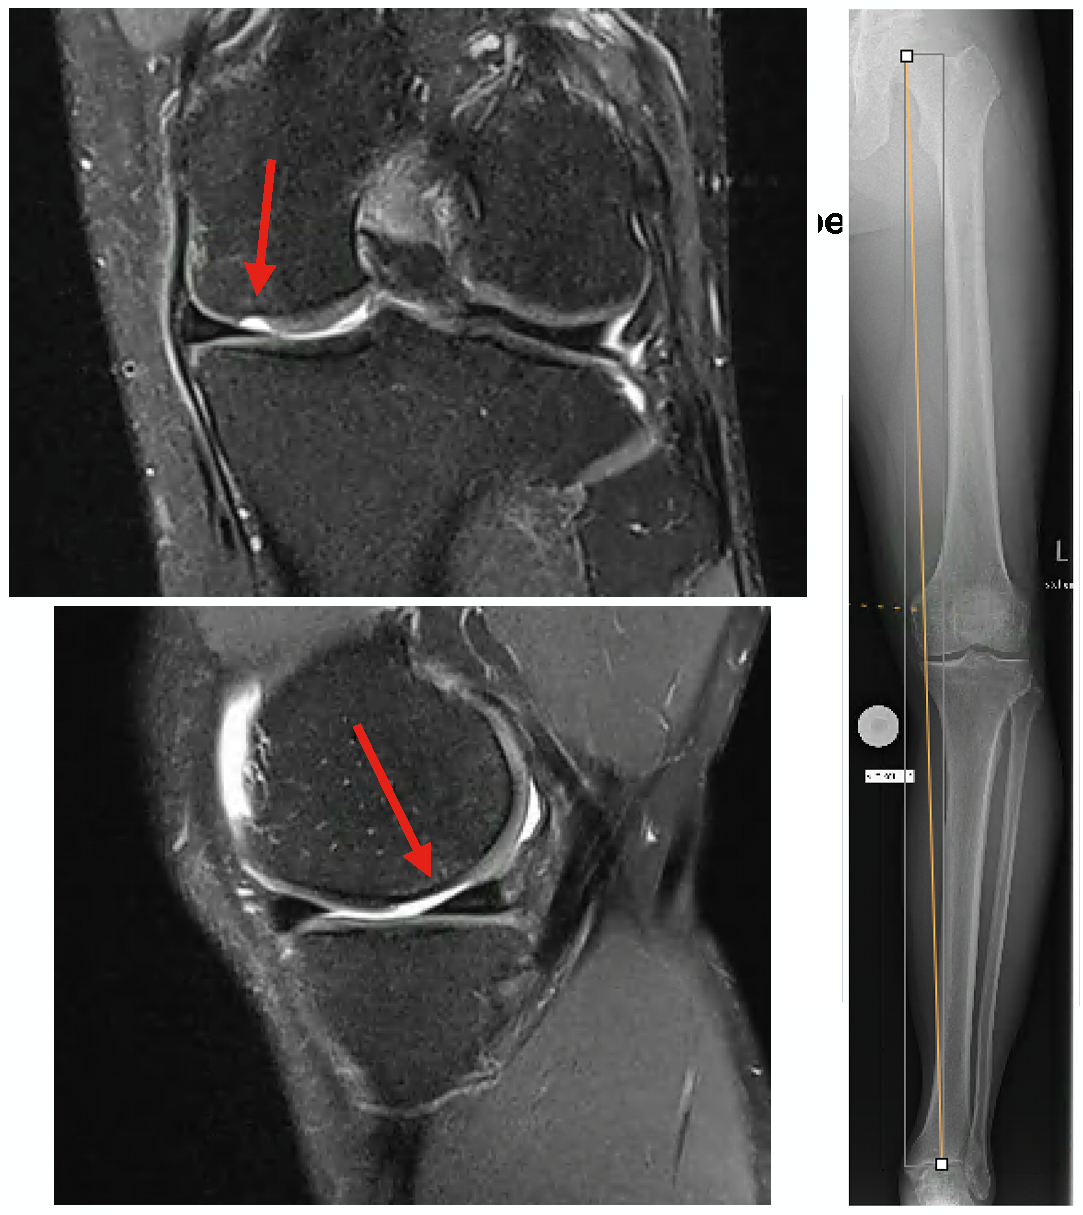

Technique Approches thérapeutiques de régénération du cartilage combinées à une ostéotomie de réalignement de l'articulation du genou , Boris Ivanovas Sportklinik Ravensburg [Sports Clinic Ravensburg] Bachstr. 57 88214 Ravensburg Allemagne N°314 - Mai 2022 ● 26 min de lecture